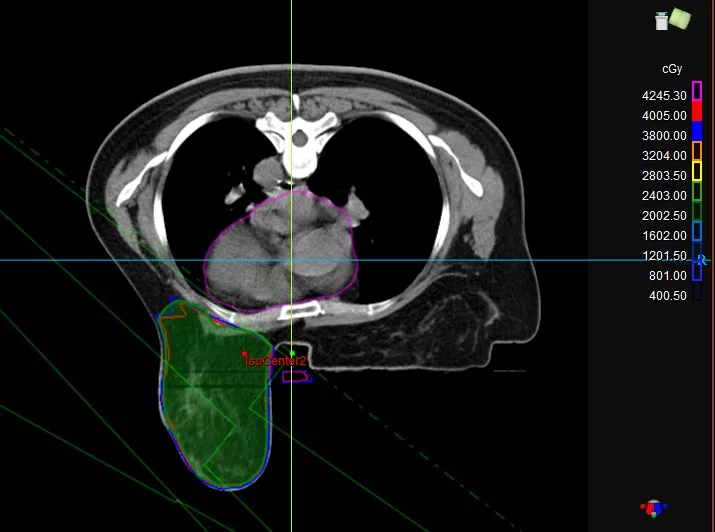

技术手段3:俯卧位照射技术

俯卧位照射技术,对于保留乳腺的患者,如果乳腺相对较大,可以采用俯卧位。俯卧位的患者,乳腺会从胸壁垂下来(图2)。与仰卧位相比,乳腺拉长,宽度减小。这种方式既可以减少左侧乳腺癌的心脏剂量,也可以减少患者肺照射体积。这种技术的难点在于患者摆位的固定和重复性,需要专用的体位固定设备。

图2